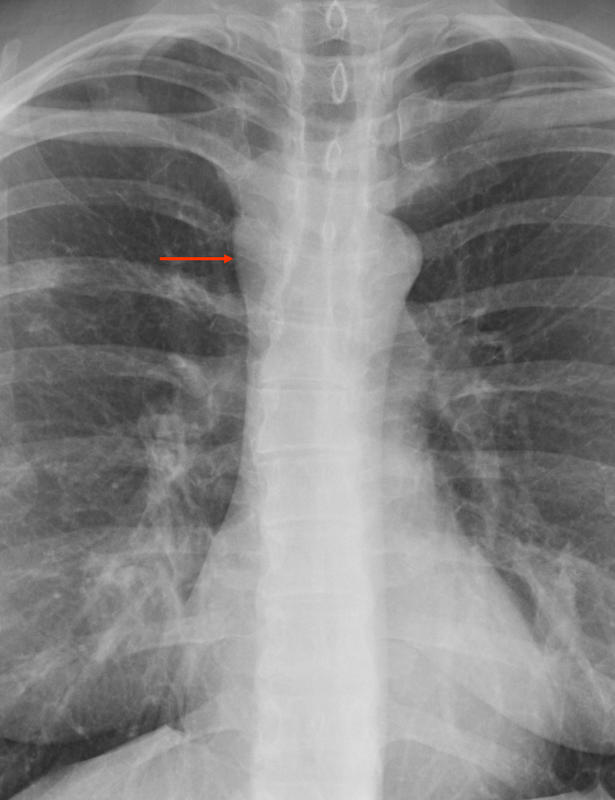

Gallery Mediastinum Miscellaneous Foregut cyst (and RML pneumonia)

Foregut cyst

(and RML pneumonia)